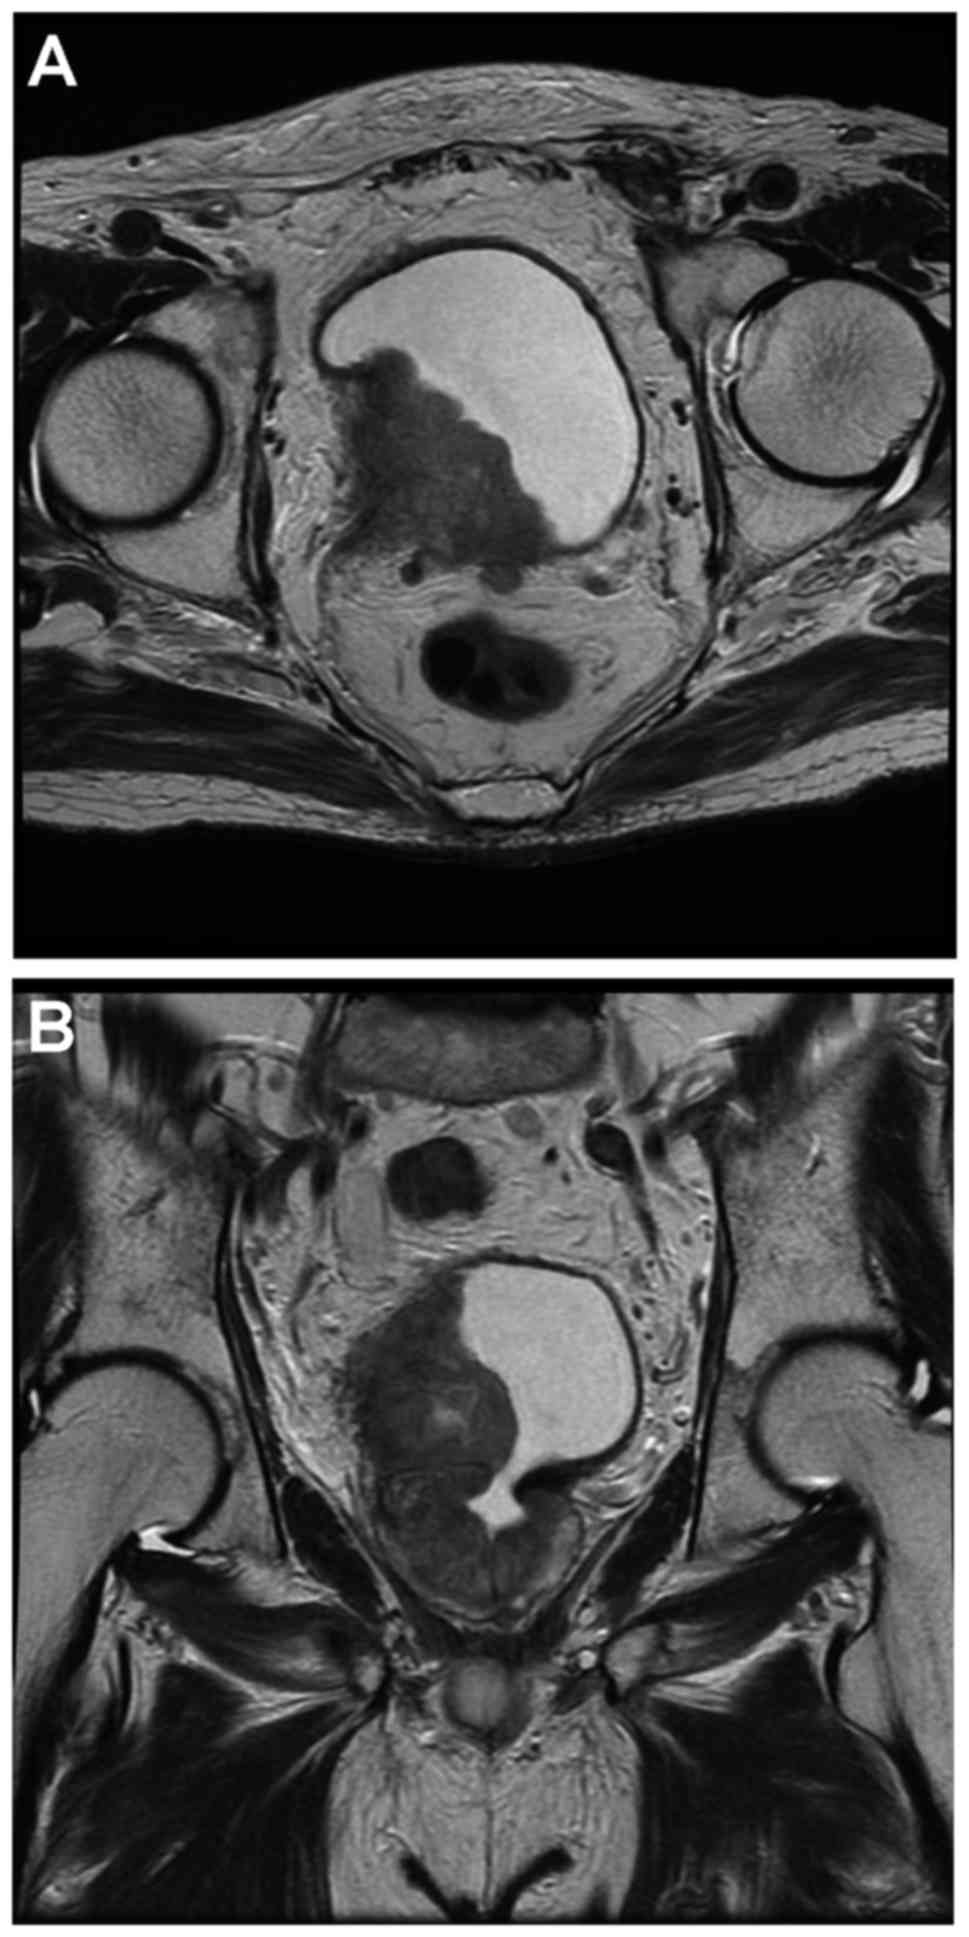

An 89-year-old male visited a local hospital with the chief complaint of gross hematuria and voiding difficulty. The patient had no past medical history and was not taking any anticoagulants. Computed tomography of the abdomen and pelvis showed a tumor on the right wall of the bladder and a right hydronephrotic atrophic kidney caused by tumor obstruction. The serum creatinine level was elevated to 1.44 mg/dl (normal range, 0.43–1.08 mg/dl) (Fig. 1). Magnetic resonance imaging showed that the bladder tumor was invading the perivesical tissue macroscopically (Fig. 2). The patient was referred to Saitama Medical University International Medical Center (Saitama, Japan) for treatment.

Figure 2.

Magnetic resonance image showing a tumor on the right wall of the bladder, obstructing the right orifice and invading the perivesical tissue macroscopically. (A) Axial slice and (B) coronal slice.